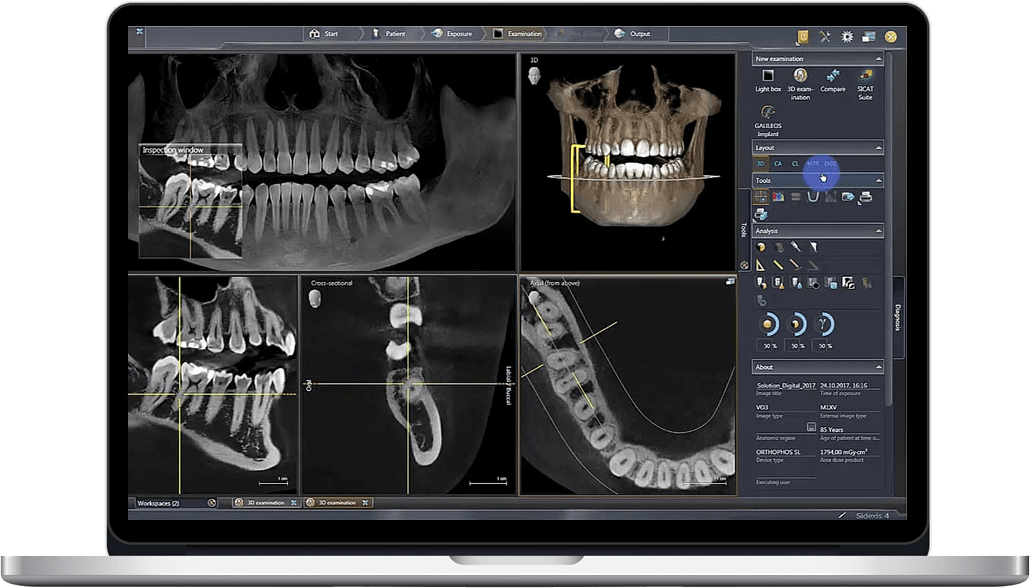

Technical Deep Dive: CBCT Imaging Systems – Engineering Principles & Clinical Impact

Core Technology Architecture: 2026 Advancements

2. AI-Driven Reconstruction: Beyond FDK Algorithms

Clinical Accuracy Improvements: Quantified Metrics

Workflow Efficiency: Engineering-Driven Gains

Quantitative Analysis Pipelines